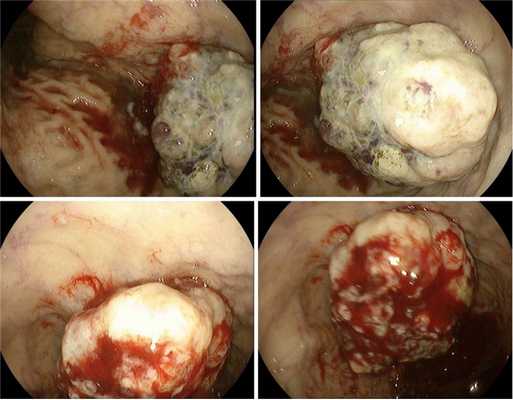

Пациенка 42г.В анамнезе: эрадикация НР 18лет назад.Ухудшение в феврале 2021г.ЭГДС02.02.2021Язва угла желудка(снимок1) Гистологическое и иммуногистохимическое исследование:MALT-лимфома,НР-пол.Проведена эрадикационная терапия.ЭГДС 29.03-ухудшение(снимок2).Патогистологическое заключение: Прогрессирование MALT-лимфомы с трансформацией в диффузную крупноклеточную В-клеточную лимфому. Актиномикоз желудка.